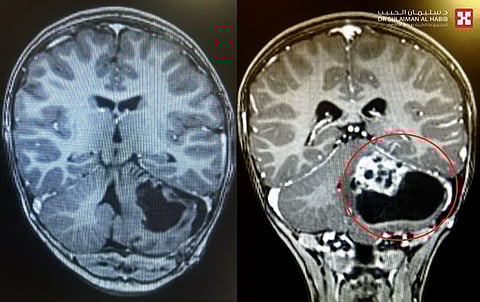

مشيرًا إلى أن نتائج الفحوصات أظهرت وجود ورم كبير ونشط بطول 6 سم في المخيخ الأيسر، على الفور تم تكوين فريق طبي من استشاريّي جراحة المخ والأعصاب وطب الأطفال والتخدير، وعقب الانتهاء من دراسة كافة نتائج الفحوصات، تقرّر إجراء التدخل الجراحي العاجل؛ وذلك للحيلولة دون إصابة الطفل بمزيد من المضاعفات الخطرة لا قدر الله.

وعن العملية قال الدكتور العيساوي: إن الجراحة استغرقت 3 ساعات متواصلة تحت التخدير الكامل، وتمّ فيها تحرير الورم واستئصاله كاملًا ولله الحمد، وذلك باستخدام تقنيات الميكروسكوب الجراحي المتطور والمراقبة العصبية، وكذلك الاستعانة بأجهزة حديثة لمساعدة الجراح أثناء العملية في دقة استئصال الورم وحماية خلايا المخ السليمة، وعدم الإضرار بالأوعية الدموية والمراكز الحيوية المحيطة بالورم، وفي نفس الوقت عدم ترك أية أجزاء منه، نقل بعدها الطفل للعناية المركزة لمدة 24 ساعة.